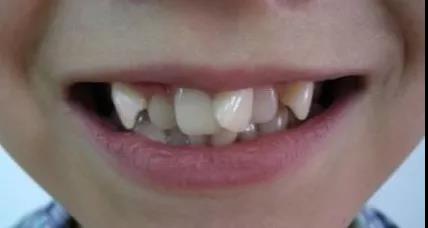

一旦乳牙因为被蛀而提前掉落,留下空隙,后方的恒牙还没有准备好就要“上岗就业”,容易找不准自己的位置,从而长歪长斜

牙齿排列错乱的孩子

宝贝的颜值也会被歪七扭八的牙齿拉低,最重要的是后期还需要通过矫正来恢复正常形态,从而花费一笔不菲的费用。

更何况,乳牙最长可服役十来年(换牙期一般为6—12岁),这期间是要参与咀嚼的,如果乳牙坏了,那宝贝怎么正常饮食啊。